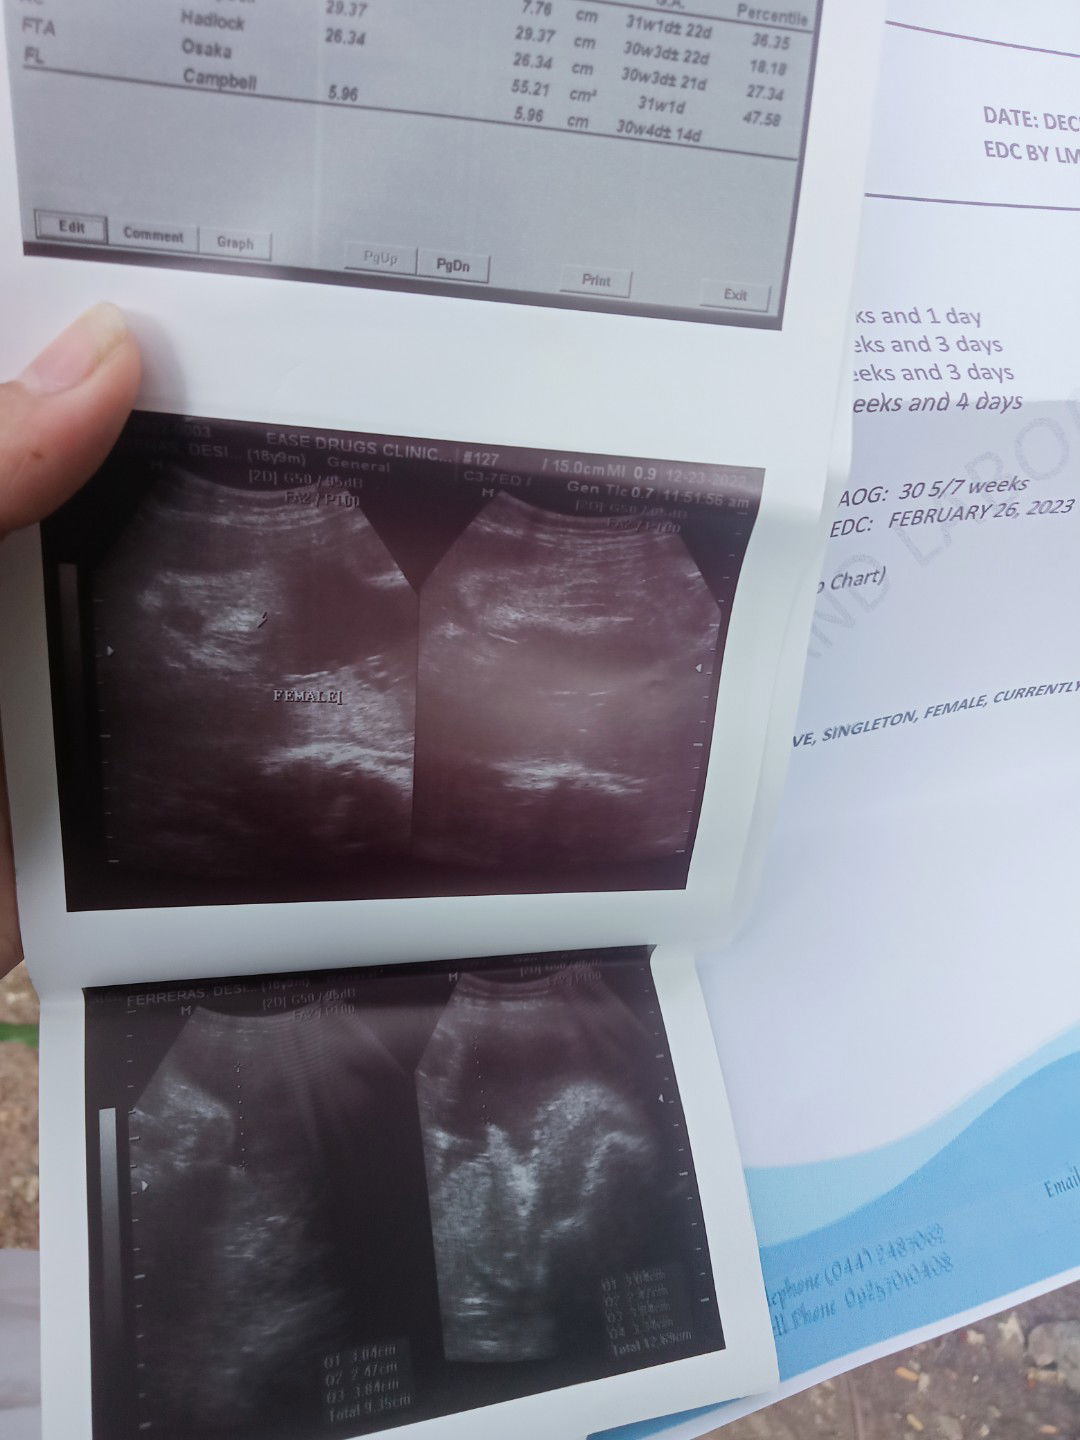

Normal lang ba ito masakit na puson at balakang sapuson po pag masakit parang na iihi po ako medyo makirot yung balakang ko nahihirapan ako gumalaw parang gusto ko patunugin sakit ng balakang ko😪 36weeks/5days napo ako ngayun bukas papo mag 6days😔